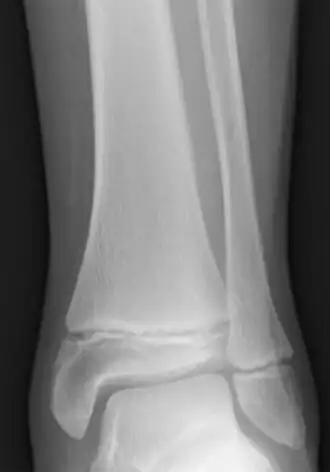

![]() Radiografia da parte inferior da perna de uma criança de 12 anos, mostrando placa epifisária em crescimento na tíbia e na fíbula.